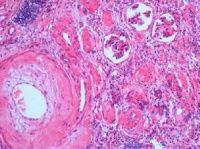

肾萎缩病理解剖学上一个名词,是根据肾脏体积与人的年龄、性别和人体的身高、体重相互比较的,相对偏小或明显缩小的一种异常现象。长时间的肾脏疾病,导致肾单位,尤其肾小球受损,使整个肾脏出现体积缩小。肾小球和肾小管部分或全部破坏,肾脏失去了生理功能。因此肾萎缩和肾功能改变是相辅相成的。肾脏大小的判断有重要的临床意义。肾脏缩小或增大,可以提示肾脏的病变。

肾萎缩是一个病理解剖学名词,也就是说肾脏萎缩,体积明显减小,也称终末期肾脏。这时肾萎缩患者的肾小球、肾小管(即肾单位)已大部分或全部破坏,肾脏已失去生理功能。